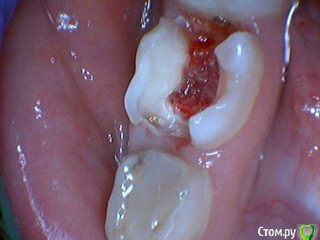

Давлетшин Опубликовано 29 декабря, 2017 Поделиться Опубликовано 29 декабря, 2017 (изменено) Друзья. Расскажите, не поменялось ли ваше отношение к пульпотеку и пр.Почему пломбы поверх пульпотеку такие ужасно жёлтые? Что сделать можно. Или что я делаю не так? "Друзья" так приятно перед новым годом. К пульпотеку не поменялось (устраивает вполне) , к пульподенту скептическое отношение, хоть и тоже работаю. Пломбы сразу желтые или через полгода - год- два? Очень тяжело что то советовать он лайн не видя как человек работает. В фото первая цифра пациент, вторая-третья номер зуба, четвертая порядок фото. Я после наложения пульпотека , стараюсь убрать излишки, или аккуратно на устья каналов накладываю, в пульповую камеру СИЦ, и сверху пломбу, Убрать излишки и со стенок, аккуратно в том числе и бором. В третьем клиническом случае, неудача. Зуб удалил сам же через 3 месяца. причину вижу в том что на рентгене не увидел (или так сделали снимок?) вертикальный тип рассасывания практически до бифуркации., может и потому что ребенок ОЧЕНЬ плохо сидел. За фото не пинайте сильно, не инстаграмм все таки,да и тяжело ребенка лечить и фотки делать. или наоборот пинайте может лучше начнем фоткать. P.s. Добавлю протокол как лечу с пульпотеком, хр.фибр.пульпит1. анестезия2. кофер ( если дает)3. раскрытие кариозной и пульповой камеры4. удаление коронковой пульпы маленьким эскаватором, я стараюсь "отрубать" пульпу5. остановка кровотечения сухим ватным шариком, 0,5-1-2 минуты6. пульпотек на устья7 СИЦ в пульповую камеру8 со стенок остатки пульпотека соскребаю бором фиссурным , цилиндрическим, там же фальц9. Пломба. может что то и зыбыл ну и оценка только позитивная перед НГ Изменено 29 декабря, 2017 пользователем Давлетшин 2 Ссылка на комментарий